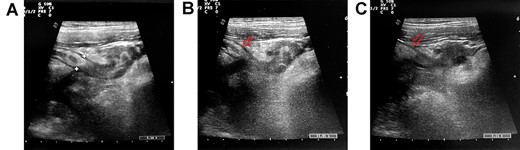

We present the case of a 22-year-old man with a history of aortic coarctation previously treated with angioplasty. The patient entered the Emergency Room on February 2022 due to pain in right iliac fossa started the day before. Medical examination showed the presence of McBurney’s sign. No fever or vomit was reported. Adult Appendicitis score was 14 (intermediate risk of appendicitis). Blood tests only indicated a slight increase in C-reactive protein (0.71 mg/dL). Abdominal ultrasound (US) revealed an appendix with diameter of 10 mm, thickened walls, a rounded image filled with liquid at the distal tip and minimal periappendicular fluid collection (Fig. 1). Computed tomography (CT) scan was not necessary. In consideration of symptoms and US results, suggesting acute appendicitis, the patient underwent laparoscopic appendectomy. The diagnosis of acute appendicitis was confirmed intraoperatively. A mucocele of the distal tract of the appendix was observed, according to US report. Meckel’s diverticulum was not found. Bowel opening to stool occurred on postoperative day (POD) 3 and oral intake was resumed on POD 1. Postoperative course was uneventful and the patient discharged on POD 3. Histological examination reported a specimen of 6 cm in length, with diverticulitis/peridiverticulitis of the appendix and acute suppurative appendicitis (Fig. 2). Three diverticula were observed with the following maximum diameter: 9 mm (distal tip with abscess), 6 mm and 4 mm (distal appendix).

The abdominal US evidences a thickened appendix with circular protrusion at its distal tip (A). Periappendicular collection is visible (B–C, red arrow indicates the appendix).

Although CT scan represents the best radiological exam for the characterization of this condition, experiences with US are available in the literature [12, 13]. Kubota et al. [12] reported the US diagnosis of AD in a 30-year-old female. US scan revealed an enlarged appendix with multiple hypoechoic lateral small pouch-like projections. The surrounding fatty tissue appeared hyperechoic due to inflammation of the mesoappendix. Iki et al. [13] also reported the case of appendiceal diverticulitis diagnosed with US scan. In this 84-year-old man images showed an appendix of 20 mm on cross section surrounded by protruding outpouches. These rounded projections appeared as hypoechoic lesions with thin hyperechoic border in the periphery. In our case, US showed the presence of a single circular hypoechoic protrusion at the distal tip of the appendix, intraoperatively described as a mucocele. Surrounding hyperechogenic fatty tissue and fluid collection were also present, confirming the characteristics indicated by the aforementioned authors.